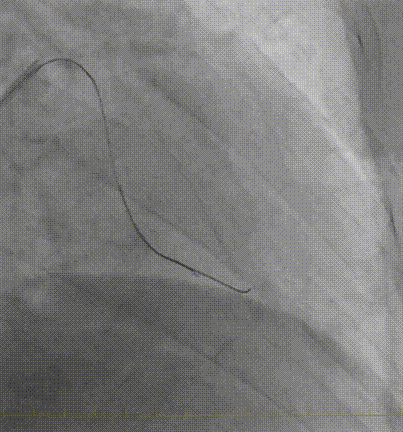

IVUS确诊夹层特征(图1F-G,视频3):

真腔受假腔压迫,假腔延伸至钙化斑块深部

LAD开口内膜撕裂,左主干未见明显夹层

图 1. 术中冠状动脉造影、IVUS及随访造影

F-G. IVUS:真腔受压,假腔延伸至钙化后方,内膜撕裂(黑色箭头)